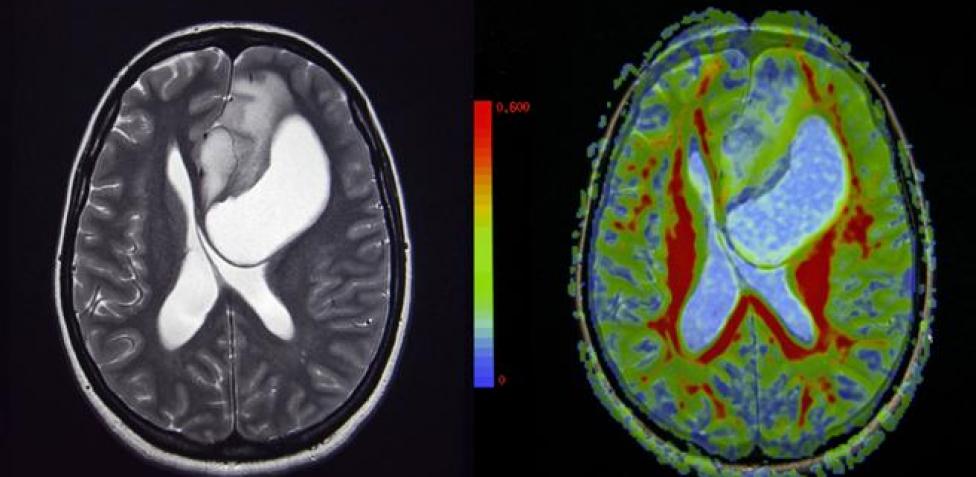

El glioma difuso intrínseco de tronco, o también conocido como DIPG, es el tumor cerebral más común en los niños, además del más letal, hasta ahora. Una investigación donde ha participado la Clínica Universidad de Navarra ha modificado un virus del catarro para destruir las células cancerosas de este tumor.

Sin embargo, una investigación donde ha participado la Clínica Universidad de Navarra ha modificado un virus del catarro con el objetivo de destruir a estas células cancerosas, y así ha sido. Gracias a este nuevo descubrimiento científico, las esperanzas de supervivencia ante este tipo de tumores son cada vez mayores.

El estudio clínico se inició en el 2017, hasta enero de 2020, con un total de 12 pacientes de entre 3 y 18 años, el cual logró aumentar la supervivencia de los participantes de los 12 meses a los 17,8 meses gracias al uso de un adenovirus, que se replica en células tumorales en pacientes con tumor cerebral recién diagnosticado.

Sin embargo, la estrategia demostró una gran efectividad, ya que nueve de los pacientes lograron reducir el tamaño del tumor cerebral, además de mostrar respuestas muy favorables. La supervivencia media se elevó a 17,8 meses.